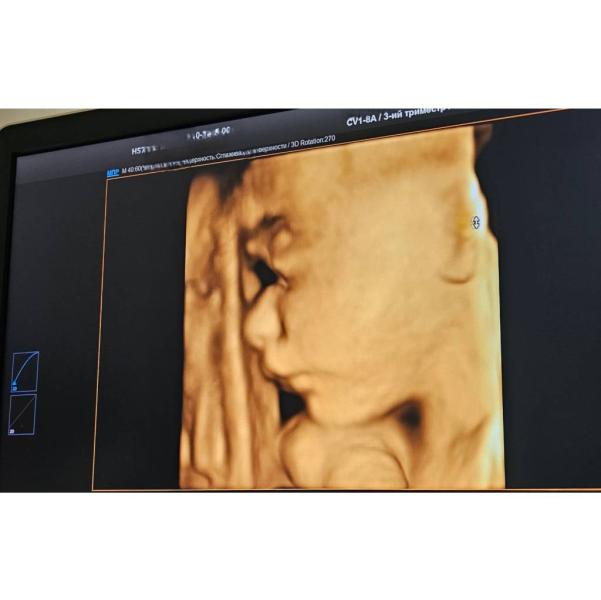

Наш малыш🥹💙

Опережает на 10 дней, 1309гр, наш крепыш💪🏻

Всё-таки, похож на мужа😅 а я была уверена, что будет на меня похож😅

#28неделя